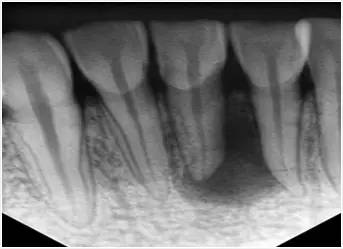

1、术前拍摄X线片

在根管治疗过程中,在根管治疗术前拍X线片,以帮助诊断,了解髓室的位置和根管数目及形态,测量根管工作长度及日后随访和评价疗效提供对比的依据。

2.X片:牙周膜间隙正常或轻度增厚,原有根尖病变缩小或消失;根尖未发育完全者,术后3—6个月逐渐形成;根管三维充填,根充物距根尖0.5—2.0mm。